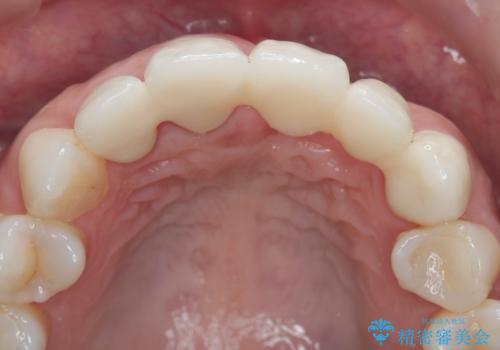

抜歯時に可及的に歯肉のボリュームを保つよう骨充填材とコラーゲン製剤による填塞を行い審美的かつ機能的なブリッジとなるよう治療を進めます。

一件綺麗に見えるセラミックも適合や精度が悪いと、内部で虫歯が進行し亀裂や破折、悪臭の原因となることがあります。